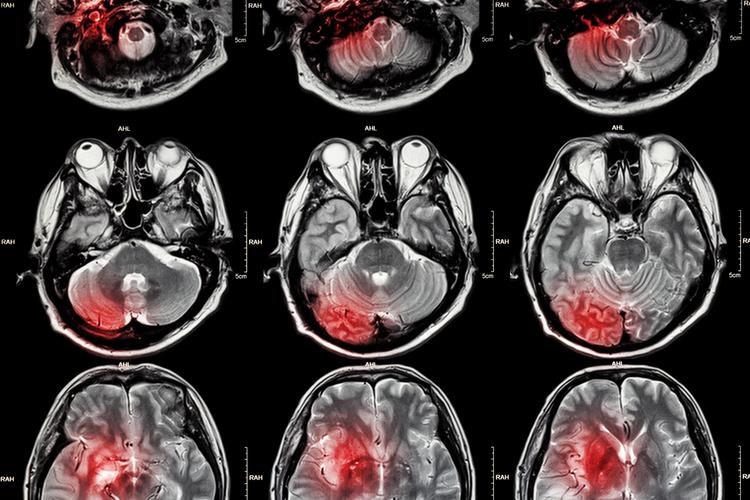

要理解一个基本背景:大脑是一个耗氧量极高的器官,它的血液供应必须非常充足和稳定,任何原因导致大脑局部区域的血液供应中断,都会造成脑组织缺血、缺氧,最终导致脑细胞(神经元)死亡。

“缺血灶”和“脑腔梗”都是脑组织曾经缺血坏死的“遗迹”或“疤痕”,它们在核磁共振(MRI)上表现为信号异常的区域,是医生判断脑血管健康状况的重要依据。

为什么会出现这些病灶?常见原因

这些病灶的出现,通常不是偶然的,是身体长期处于不健康状态的结果,主要与以下因素密切相关: